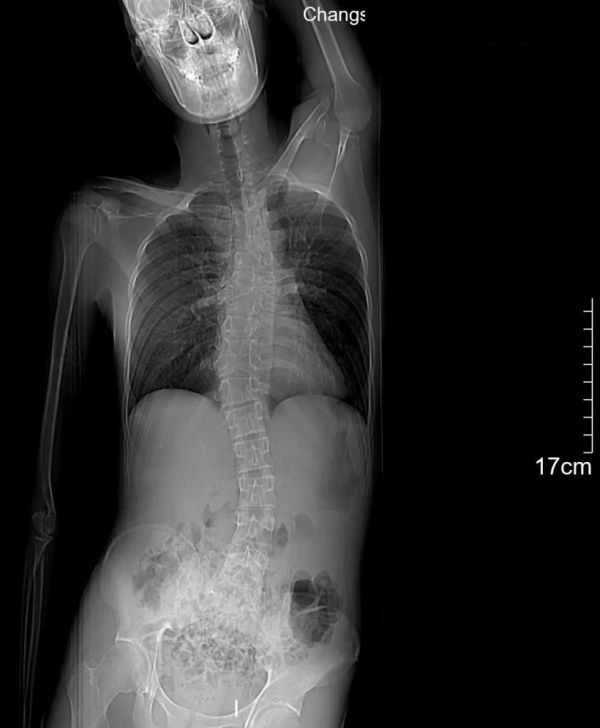

2、術(shù)前評(píng)估

DR全脊柱正側(cè)位(頸胸腰)、CT(Bending位)

DR全脊柱正側(cè)位(頸胸腰)

DR全脊柱正側(cè)位 影像所見(jiàn)

脊柱過(guò)伸過(guò)屈位示胸椎T3-12椎體不同程度變扁,多發(fā)椎間隙變窄,胸椎活動(dòng)度欠佳。

影像結(jié)果

胸椎多發(fā)椎體改變:考慮發(fā)育畸形,胸椎活動(dòng)度欠佳。